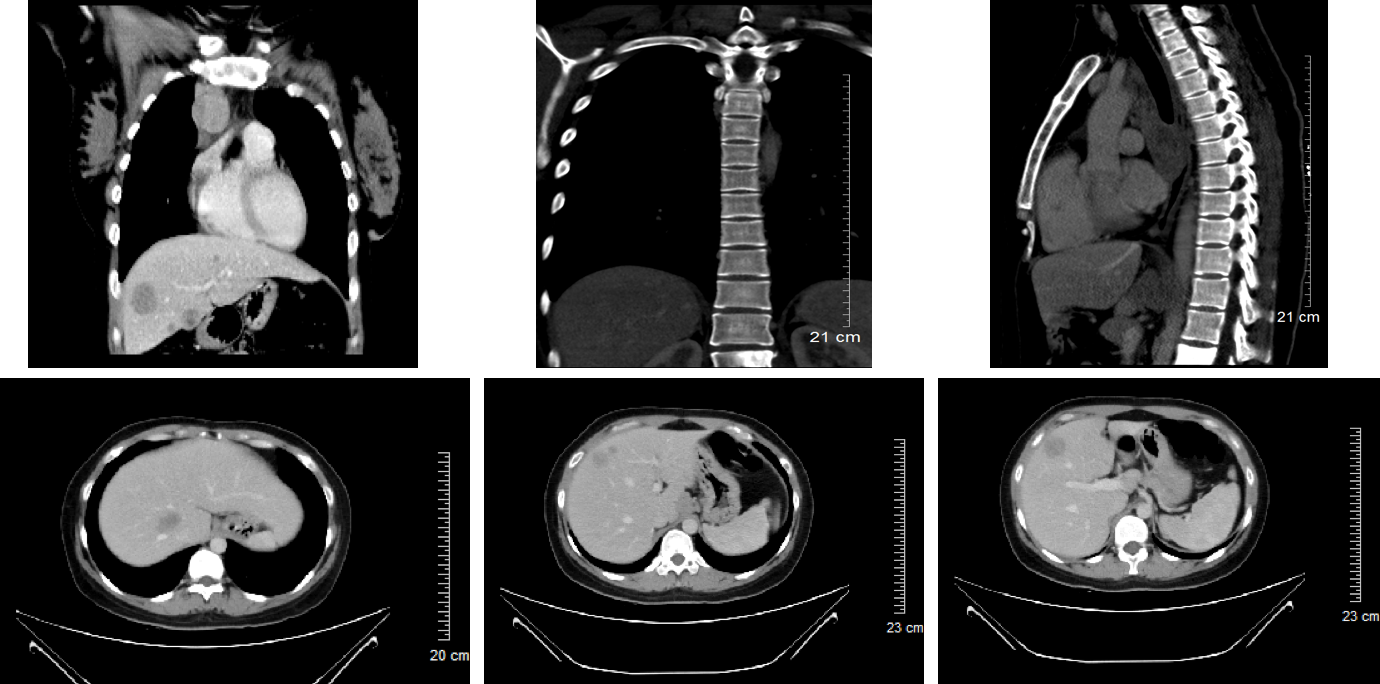

• 2018-12-17患者顺产1足月女婴,次日就诊于当地医院,查胸片发现右肺占位性病变。肿瘤标志物检测提示:CA15-3、CA125、Cyfra21-1、TPS升高(表1)。CT检查提示1.右肺上叶近肺门处团块状软组织密度影,考虑中央型肺癌可能,伴阻塞性肺炎,并纵隔内、双侧肺门多发淋巴结转移,双肺、肝脏多发转移瘤;L1椎体及左侧附件密度增高,考虑为转移瘤;2.脾大(图1);头颅MRI检查提示头颅MRI未见占位性病变。气管纤维支气管镜检查提示右主支气管新生物生长,表明凹凸不平,触之易出血,予活检及肺泡灌洗;隆突粘膜改变,肿瘤浸润可能。送检(右主支气管)组织内见部分瘤细胞呈巢团状排列,异型明显,胞浆丰富、红染,核异型性明显核仁可见,间质纤维组织增生伴大量淋巴细胞浸润(图2)。免疫组化:CK(+)、CK7(-)、TTF(-)、P40(+)、CK5/6(部分+)、Ki-67(+, 80%) 。原位杂交:EBER(+)。免疫组化 (补,22C3):PD-L1 (+, 95%)病理诊断考虑淋巴上皮瘤样癌。

图1 患者基线肺部CT影像,右肺上叶近肺门处团块状软组织密度影,考虑中央型肺癌可能,伴阻塞性肺炎,并纵隔内、双侧肺门多发淋巴结转移,双肺、肝脏多发转移瘤;L1椎体及左侧附件密度增高,考虑为转移瘤;脾大